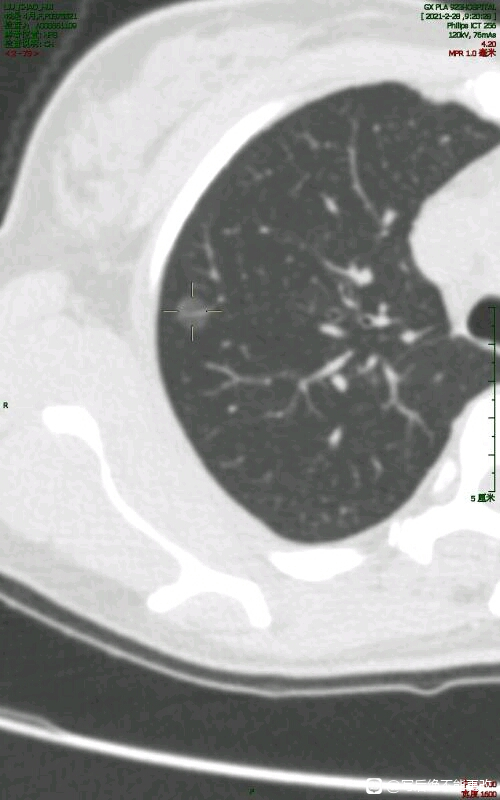

意外的是在ct检查中发现 右肺上叶纯磨玻璃结节0.9厘米 ,妇科住院部请胸外科会诊。由于胸外科很忙,会诊医生迟迟未能过来,我就挂门诊号带着片子看门诊。本想自己去的,但姐姐好像预感到什么,非要同去。门诊医生看了后说可能炎症,最坏结果为原位癌,还可观察三个月,届时再考虑手术,术前还要做个针刺定位。

初次发现磨玻璃结节至少三个月复查薄层ct,排除炎症后再精准诊断。随访结节不消失即手术,考虑微浸润腺癌,楔形切除或段切即可,别切20%。

“ 不严重,原位腺癌与微浸润腺癌之间,手术现在可做可不做 ”。听着戴主任这句宛如天庭仙乐般的话语,看着那副有些憔悴却如救世主般的容颜,姐姐心中五味杂陈,百感交集,禁不住低声抽咽起来!

不可能是良性的结节,微浸润腺癌的可能性更大。手术就手术吧,不纠结!

姐姐还没回到病房,就着急地问护士和大夫:“我现在可以咳嗽了吗?”听着都觉得好笑!回到病房刚在病床上整理停当,姐姐就开始按照吴医生的嘱咐做起了恢复动作,深呼吸,脚回勾放松,咳嗽吐痰,还比起手势“欧耶”!我估计她是想明天就出院!事情很清楚了,戴主任确实又做了一台假手术,而且一网打尽3个结节,术中病理报告:1个微浸润腺癌和2个原位腺癌,和戴主任术前预估的一模一样!